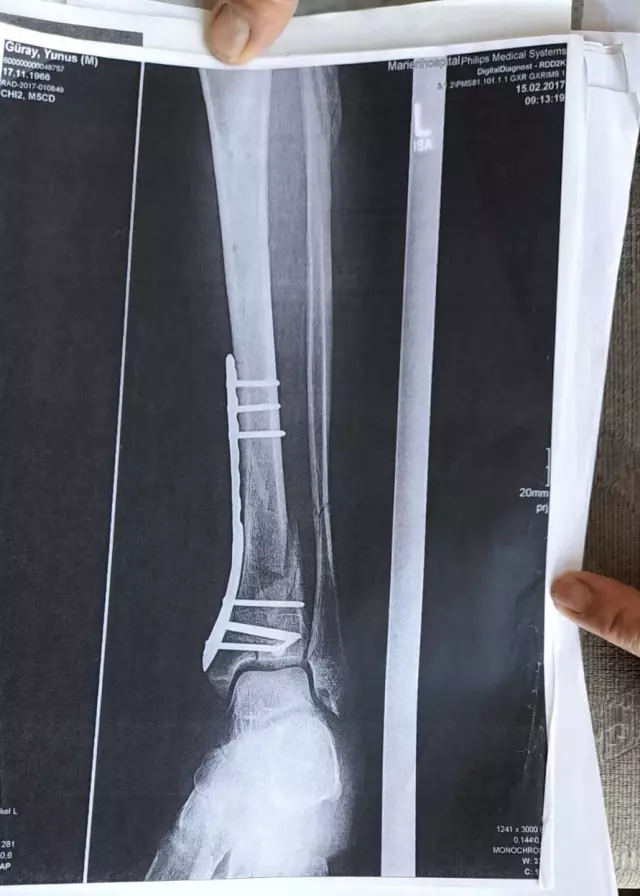

"DEMİR VAR AYAĞIMDA, SAKAT BIRAKTILAR"Olay yeriyle ilgili fotoğraf ve görüntüleri mahkemeye sunduklarını kaydeden Güray, "Ömrümü yediler, demir var ayağımda, sakat bıraktılar. Ayağı keseceklerdi neredeyse. Şu an kalıcı sakatlık var. 1 sene kendime gelemedim, 2 haftada bir ameliyata giriyordum. Almanya'da 3 ay hastanede kaldım ve ayağımda yüzde 3'lük engel oluştu" diye konuştu.

"O ÇUKURLARI 3 AY SONRA KAPATTILAR"Tazminat miktarını düşük bulan Yunus Güray, şunları söyledi: "Benim uçak masrafım sadece 22 bin avro tuttu. 9 yıl oldu, bir tane çukur değildi. Adamlar kazmış, kazmış, bırakmış. Tam merkezde bu olay, hani ormanda bir yerde olur, 'Tamam benim de hatam var. Gittim de düştüm' derim. Ama şehrin merkezinde, etrafı çevrili değildi. Yemyeşil alan, gece vaktiydi. Ben mahkemeye verdim, o çukurları 3 ay sonra kapattılar. 6- 7 yerde kazılmış çukurlar vardı. Bir tane değildi. Ayağımda hala demir var. Adil bir karar olmadı."